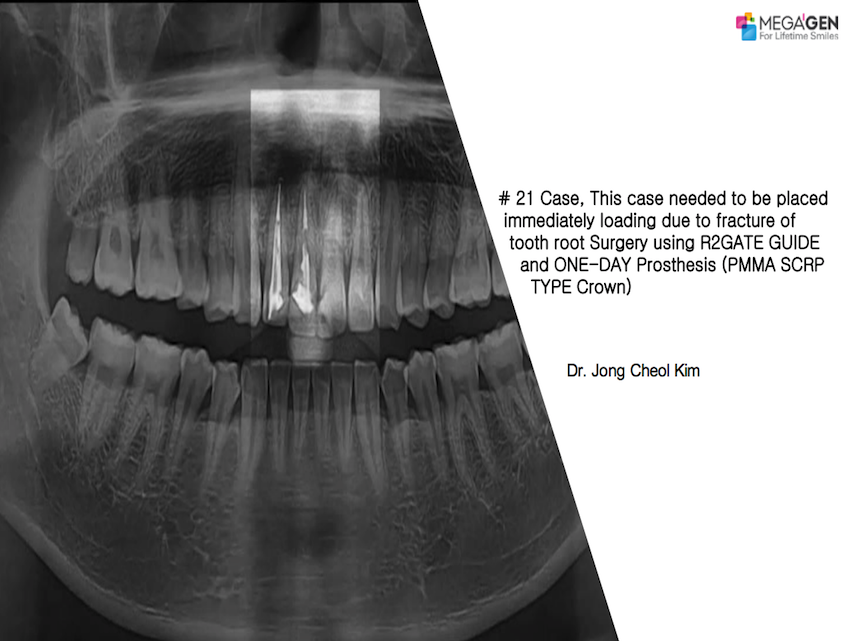

This case needed to be placed immediately loading due to fracture of tooth root Surgery using R2GATE GUIDE and ONE-DAY Prosthesis

Dr. Jong Cheol Kim,Digital ONE-DAY Implant,Maxillary Anterior,#21,Immediate loading,AnyRidge,R2GATE,R2GATE Surgical Kit(AnyRidge)